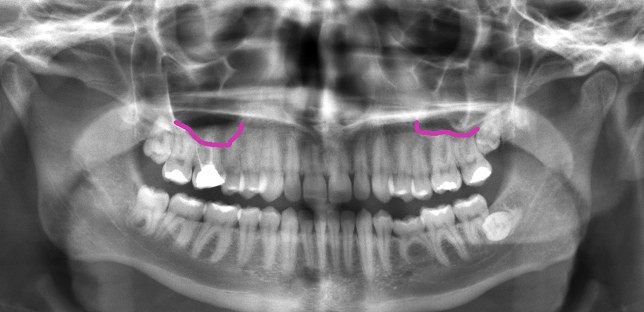

در زیر تصویر پرتوی ایکس از دهان را مشاهده میکنید که کف سینوس ماگزیلاری با خط بنفش مشخص شده است. سینوس درست بالای دندانهای بالایی قرار گرفته است بنابراین نزدیک ریشه دندانهای مولر (آسیاب) قرار دارد.

در سمت چپ به نظر میرسد کف سینوس، زیر ریشه دندانهای مولر بالا قرار گرفته است اما معمولا چنین نیست و این تصویر دو بعدی به خاطر هم پوشانی موقعیت ریشه دندان و سینوس به این صورت دیده میشود و در واقع یکی جلوتر و دیگری عقب تر قرار دارد. در هر صورت با این تصویر به خوبی متوجه میشوید چرا عفونت سینوس میتواند با دندان درد اشتباه گرفته شود.